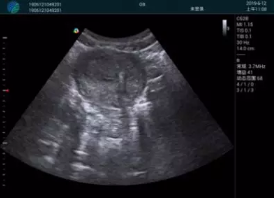

腺體內(nèi)部清晰顯示一低回聲塊影,形態(tài)不規(guī)則,邊界模糊,邊緣呈毛刺狀,內(nèi)部見砂礫樣鈣化

M20引導(dǎo)下穿刺活檢術(shù)